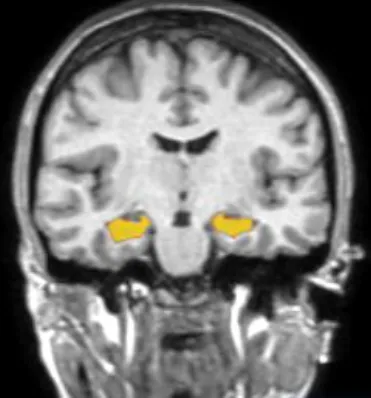

CogSmartは2つの主なサービスを展開しています。まずは、AIで海馬の健康を可視化する「BrainSuite」です。このサービスでは、頭部MRI検査とAI解析を組み合わせ、認知症の早期リスクを客観的に判断できます。さらに、行動変容を促すアプリ「BrainUp」では、生活習慣の改善によって海馬を“育てる”ことができる方法を提供しています。